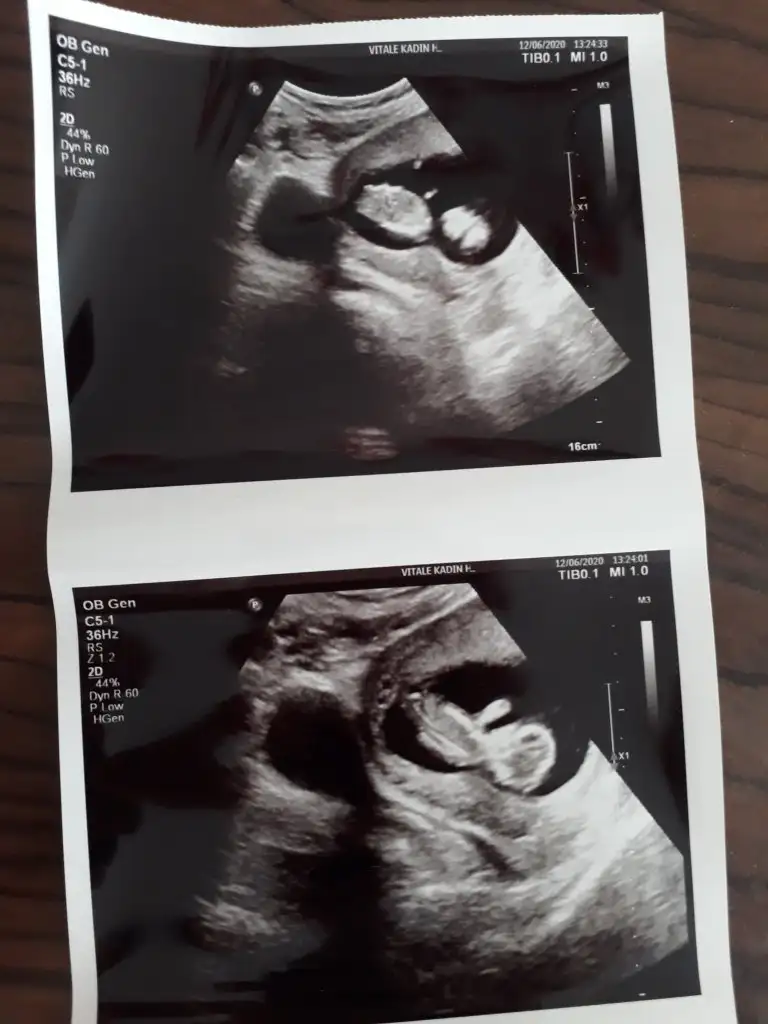

Kız gibi emin olmadım ögrenmedinizmi 24 hafta görünüyor takviminiz

Bencede kız gibi yaKız gibi emin olmadım ögrenmedinizmi 24 hafta görünüyor takviminiz

Vallaha bencede tüm belirtiler de kız diyor çünkü ilk hamileliğimin tam tersiBunlara göre kız sanki nette değil usg ama kese kız yönündedetaylı taramamı neydi 20-24 hafta arası giriliyor orada netleşmiş olmalıydı

Emin olmamakla birlikte kıza benzettimBen de 12+2 haftalığım. Doktor bir tahminde bulundu ama görebilirseniz bana da tahminde bulunabilir misiniz.

Başka yok malesef ultrason. Tekrar gittiğimde atarım yine. Doktor bir çıkıntı gösterip erkek dedi ama kesin değil demişti. Ultrasonda göremedim ben de o çıkıntıyı.Emin olmamakla birlikte kıza benzettimnet değil nubu degil baş taraftan almış usg varsa başka usg paylaşın 11 hafta yada olursa 13+ hafta paylaşın